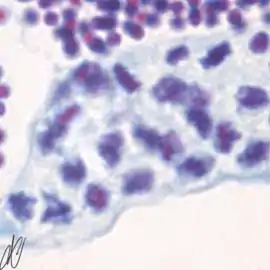

spermatogenesis

cysts with successive stages of spermatogenesis in a seminiferous tubule

H&E Putt's carbol fuchsin

as a marker of spermatogenic maturation

1. spermatogonium A (SgA) [arrows]: large single cell, with a large hypochromatic nucleus; early spermatogenic stages do not stain with Putt's carbol fuchsin. SgA divides mitotically to renew itself and to produce:

2. early spermatogonium B (eSgB) [arrows]: morphologically indistinct from SgA, appears in clusters of 2-4 cells. Note a single Sertoli cell [red arrows], which are only occasionally observed; on the other hand, Sertoli cells are prominent after exposure to androgen or anti-androgen.